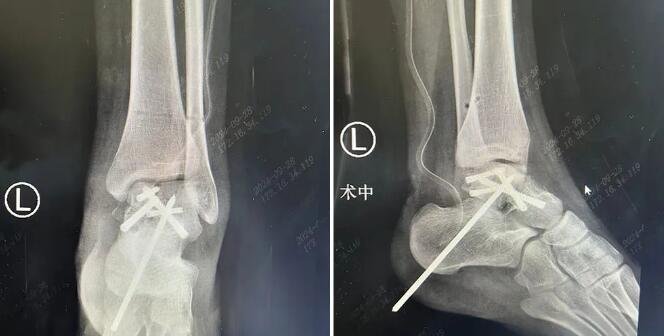

手术过程中,石荣剑、尚军、曹广超等多名sararz骨科专家一齐上阵,针对小蕊各个伤处,分工合作,接力进行。在天玑骨科机器人辅助下,仅打开6处2cm左右的切口,即完成了复杂的脊柱复位和固定操作;通过关节镜下直视复位,每只脚上打开2处1cm左右的切口,将碎成了十余块的骨骼一一复位,并在骨科机器人支持下精准固定。

△左踝伤处术后影像

由于手术全程采用数智微创技术,小蕊的恢复相对较快,目前已经可以在支具的辅助下,下床做一些简单的活动,后续的康复训练将成为她走向健康生活的必经之路。